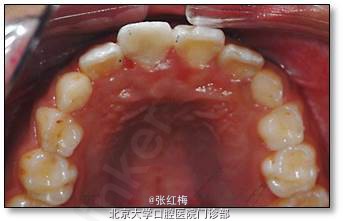

11牙冠龈1/3折断,牙髓暴露约6×1mm2,灰紫色,略有增生,叩(±),不松,龈未见异常,

21牙冠龈1/3釉质横形隐裂,叩痛(-),不松,冷测同正常对照牙,龈未见异常;

11、21正中牙合及前伸牙合未见明显牙合创伤;

处理:11去旧充填体,11及断片牙体预备(颊侧备斜面,髓腔备固位形,舌侧备排溢道),one-coat bond+纳米树脂粘接断冠,调牙合,抛光。